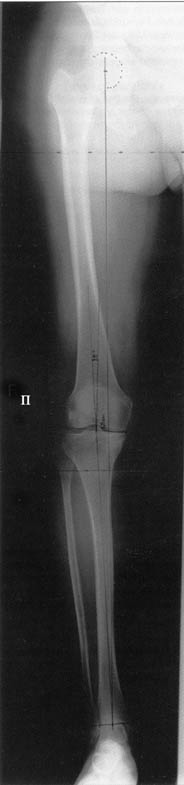

AC> Вот, с учетом и без учета, и на разных уровнях...

AC> Саша Артемьев, может, для данного случая свой вариант нарисуешь?

Из приведнной схемы не совсеим понял что означают разноцветные линии.

И зачем латерализация периферического фрагмента. Я всегда делаю медиализацию. См схему. И для данного случая медиализация подходит как нельзя лучше.

a> Из приведнной схемы не совсеим понял что означают разноцветные линии.

Черные - это нынешняя механическая ось. Красные - это планируемая правильная ось.

a> И зачем латерализация периферического фрагмента.

;-) Читайте Палея. Стр. 114-115.

a> Я всегда делаю медиализацию. См схему. И для данного случая

Медиализация - это чисто эстетический прием, как я понимаю. Поскольку если делать остеотомию ниже вершины деформации, для восстановления оси надо делать смещение по ширине, в данном случае как раз латерализацию.

А вот на схемке без осей - там на разных уровнях (который правильнее?) устранение варуса чисто открытым клином без медиализации-латерализации. Если как-то так сделать - этого недостаточно будет?